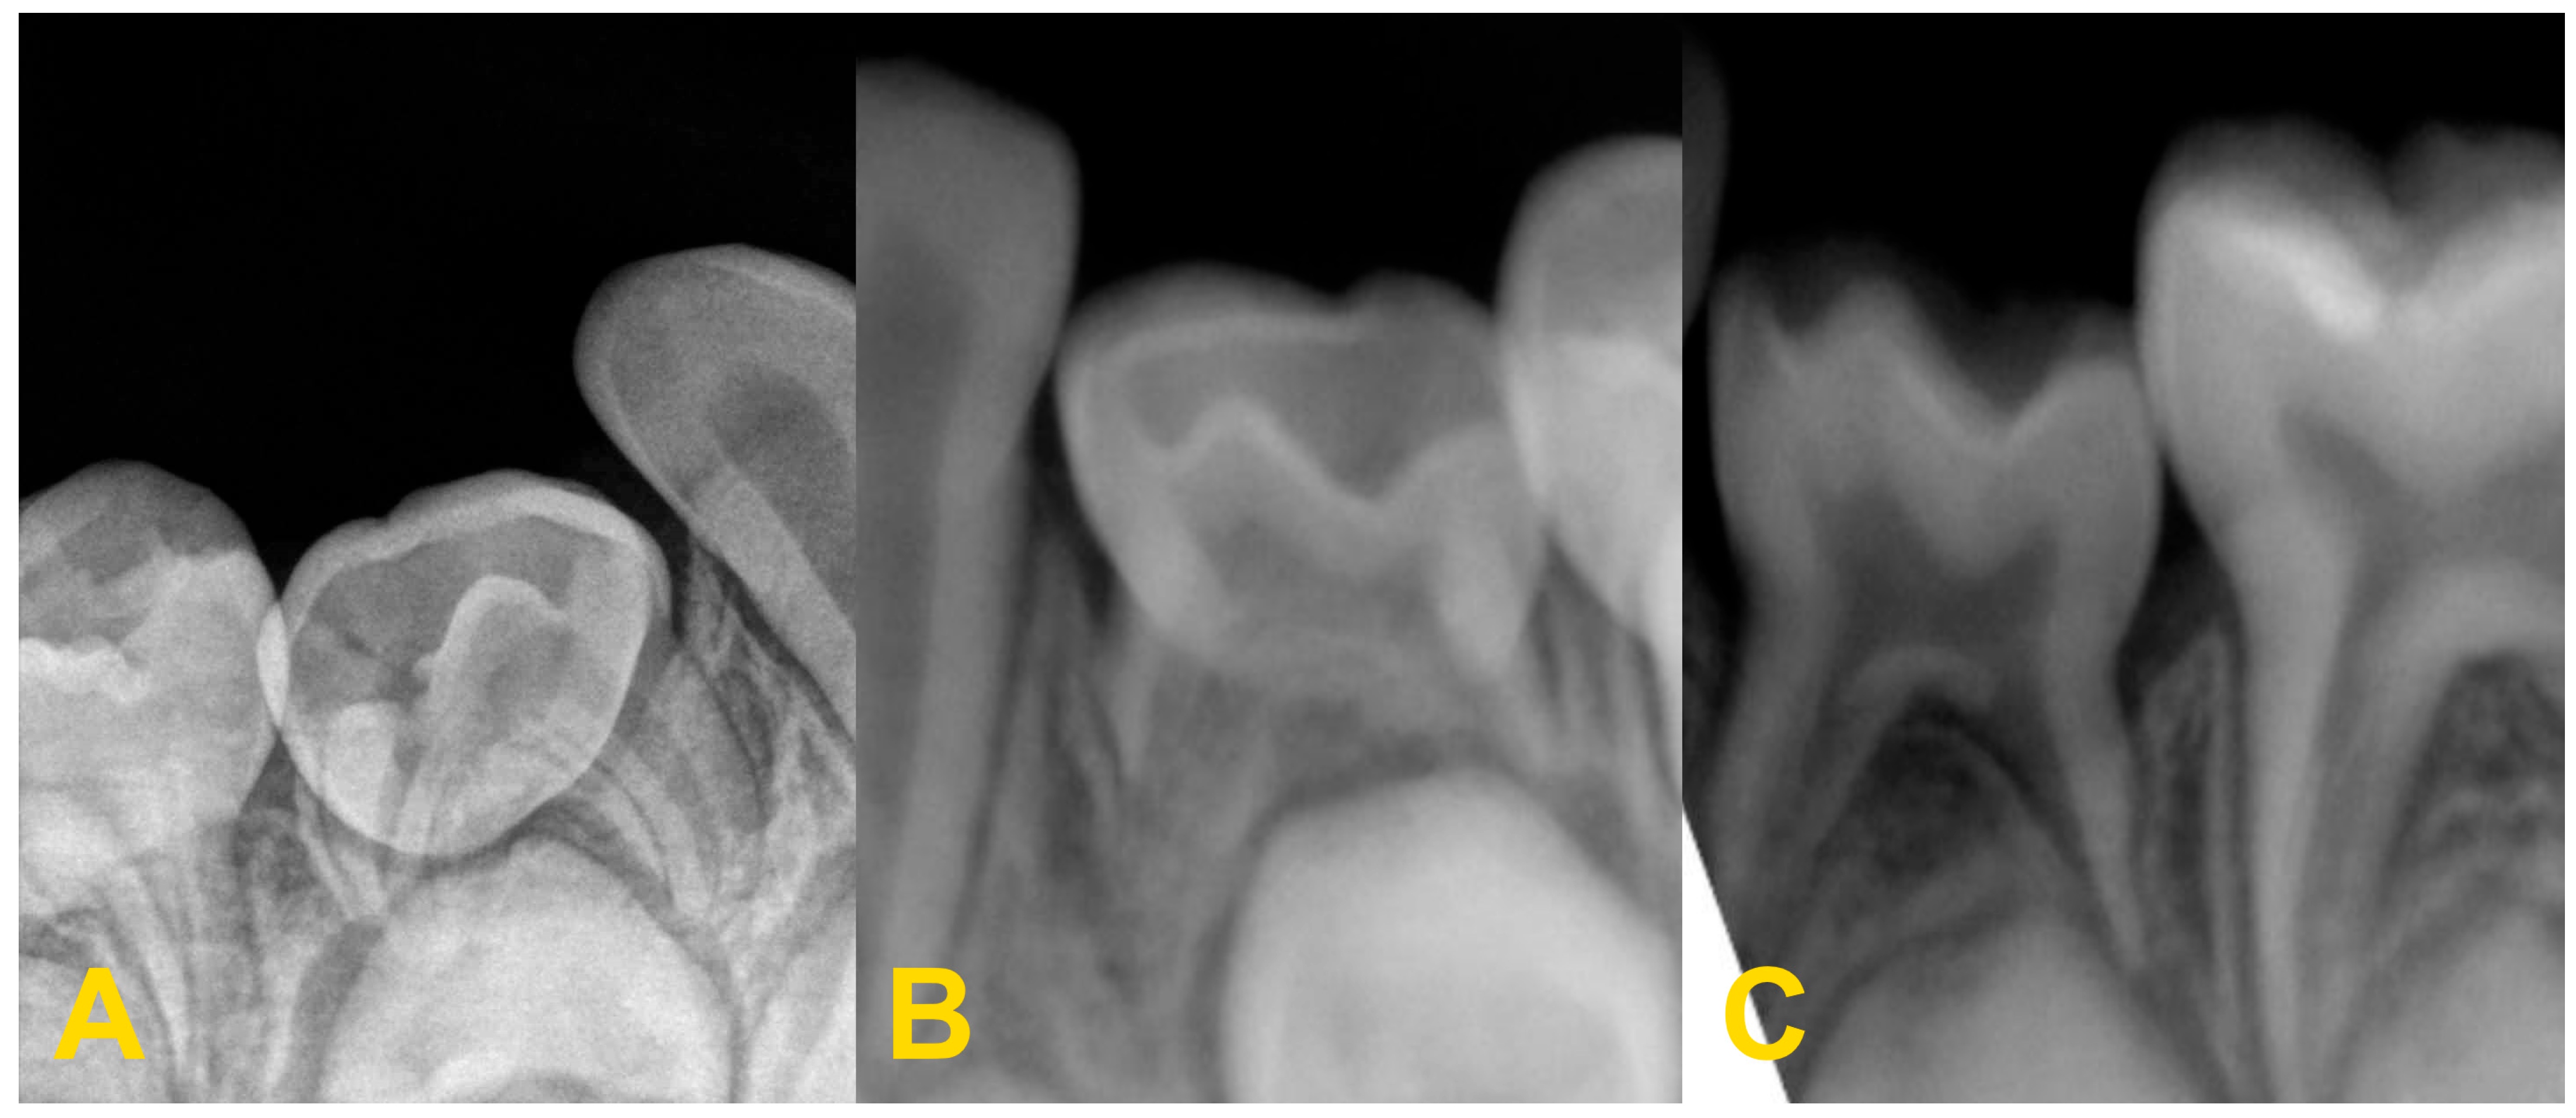

2. Diagnostics and Treatment